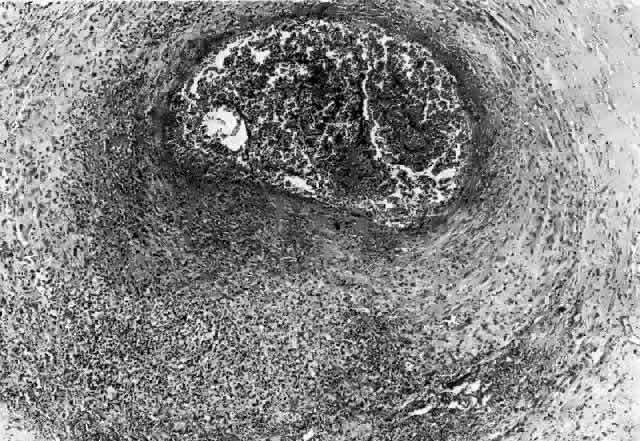

Histopathology

In general, idiopathic orbital inflammation is polymorphic (Figs. 5 AND 6).3,6,7,33,87,88 The cellular response seen in this disease consists of lymphocytes, plasma cells, macrophages, histiocytes, occasional neutrophils and eosinophils, epithelioid cells, and fibroblasts. These are present in varying numbers, depending on the chronicity of the inflammatory process. Intranuclear Dutcher bodies and intracytoplasmic Russell bodies may be present within many of the plasma cells since they actively participate in the inflammatory response. Children tend to have a significant number of eosinophils in their biopsy specimen. Lipogranulomatous inflammation with fat necrosis may also be present. However, the presence of noncaseating granulomas is relatively uncommon.89 This is often associated with foreign body giant cells that are responding to the release of lipid. Perivascular lymphocytic cuffing and capillary proliferation are quite common.3 Occasionally, lymphoid follicles may also be seen.

Fig. 6. Histopathologic sections demonstrating the various pathologic findings associated with idiopathic orbital inflammation. Most commonly these include lymphoid follicles, granulomas, collagen deposition, and a diffuse mixed inflammatory cell infiltrate. The normal tissue architecture is frequently disrupted by these changes. A. Many lymphoid follicles are scattered throughout orbital tissue (H&E, × 63). B. Cells of follicular center are lighter and larger than mantle of mature lymphocytes that surround the germinal zone (H&E, ×160). C. Lacrimal gland elements have undergone atrophy in advanced example of idiopathic dacryoadenitis. Fibrosis and lymphocytes have replaced a considerable amount of gland parenchyma (H&E, ×94). D. Myositis in which lymphocytes are loosely aggregated below center and infiltrate between extraocular muscle fibers (H&E, ×160). E. Cuffing of small vessels by mature lymphocytes. Note loose edematous interstitium between disrupted muscle fibers (H&E, ×240). F. Progressive fibrosis of retrobulbar fat (H&E, ×25).